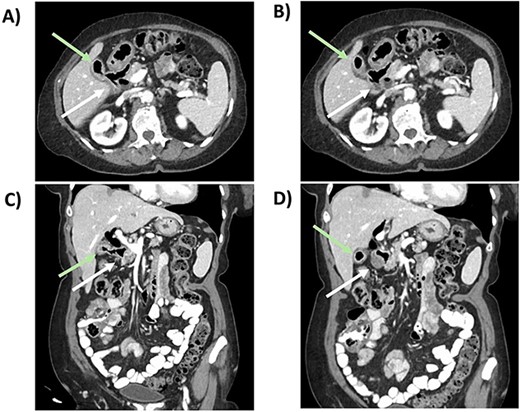

She underwent a diagnostic laparoscopy revealing a transition point secondary to the impacting 3-cm gallstone in the mid-jejunum. A small laparotomy was used to perform an enterotomy, stone extraction, and enterotomy closure. She had an unremarkable postoperative course. After 2 months, a follow-up CT revealed pneumobilia and a likely cholecystoduodenal fistula (Fig. 2). After medical optimization, she was scheduled for an elective robotic cholecystectomy and repair of the fistula 7 months later.

CT scan from follow-up after the index procedure. A) Axial CT: cholecystoduodenal fistula; air-filled gallbladder (superior, green arrow), duodenum (inferior, white arrow), B) Axial CT: air-filled gallbladder (superior, green arrow), duodenum (inferior, white arrow), C) Coronal CT: cholecystoduodenal fistula; air-filled gallbladder (superior,green arrow), duodenum (inferior, white arrow), D) Coronal CT: air-filled gallbladder (superior, green arrow), duodenum (inferior, white arrow).